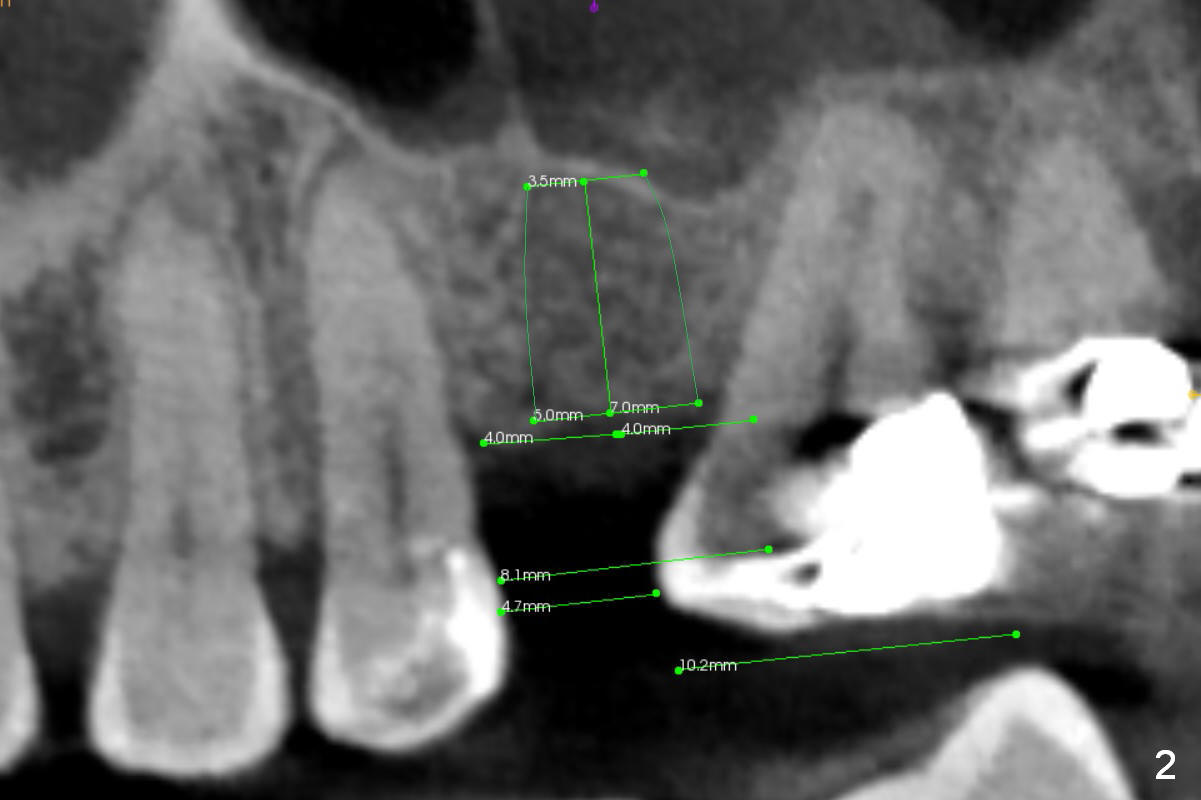

CT shows a residual root in the left maxillary sinus. In order not to re-infect the sinus, an implant at the site of #14 should not enter the sinus (Fig.2) or enters the sinus with bone graft (Fig.3,4 red circles) and more importantly PRF membrane (yellow).